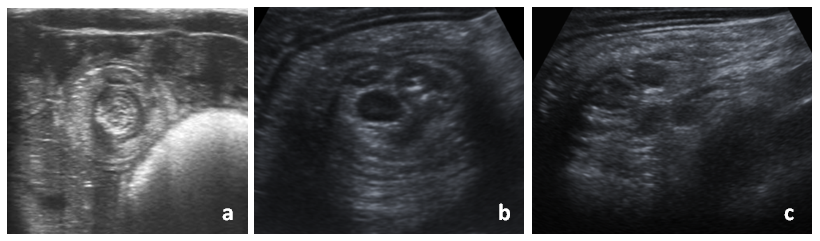

Los pacientes presentan característicamente crisis de dolor abdominal con encogimiento de piernas, seguidas de un periodo de decaimiento. Esto puede ir acompañado de irritabilidad, vómitos, inapetencia y/o deposiciones sanguinolentas (en jalea de grosella)2,3,5,10,13. En el proceso diagnóstico, además de la clínica –que es el pilar principal–, la radiología tiene un papel muy importante. La ecografía, fundamentalmente, y la radiografía simple de abdomen proporcionan imágenes características (en forma de diana, donut o pseudoriñón) (Figs. 1 y2), muy útiles para la identificación de esta patología, así como para su localización y estudio de posibles complicaciones15-20.

| Figura 1. Imágenes ecográficas de invaginación intestinal: a) corte sagital de una invaginación intestinal ileoileal (imagen en diana o donut); b) corte sagital de una invaginación ileocólica, con adenopatías en su interior; c) corte longitudinal de una invaginación ileocólica (imagen en pseudorriñón) |

|---|

![]() |